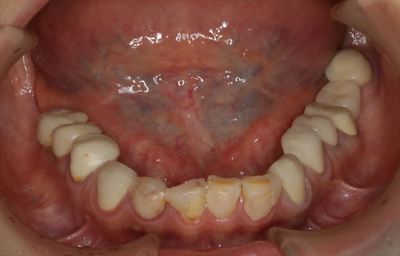

IMG_8038_R26.JPG

上顎はすべての歯がホープレスと判断し、抜歯しました。(2019.05.29)

抜歯後の歯肉が完全に治癒して落ち着くまでは総義歯とし、その後ご希望であればインプラント治療を行います。

IMG_6909_R26.JPG

下顎は咬合平面の是正とホープレスの歯の抜歯、インプラントの埋入、再根管治療、セラミックのかぶせもののセットを行います。